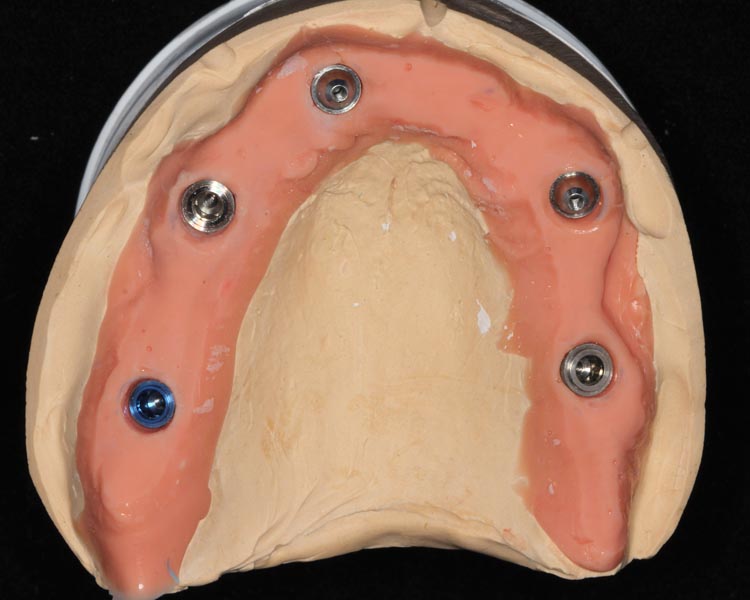

Tissue-view of the final implant bridge. Note the convex (cleansable) contours. This is a wide departure from “All-on-4” treatment which is virtually uncleansable.